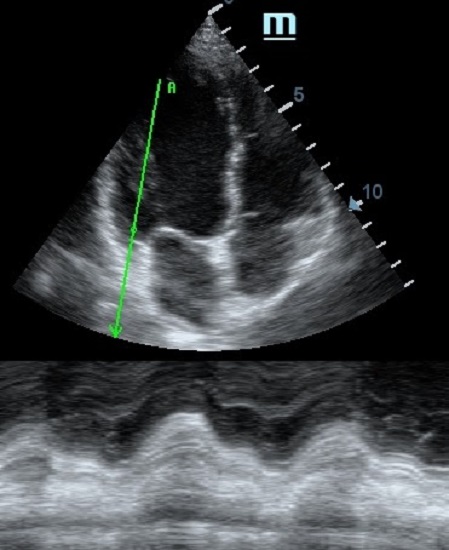

Но как же провести стандартные измерения в М-режиме, если мы его не использовали? На помощь приходит функция Free Xros M – анатомический М-режим. Имея записанную в память прибора видео петлю, мы можем провести линию М-режима в любом месте, при этом корректируя изначально не оптимальный угол.

Оценка сокращения сегментов левого желудочка на глаз постепенно уходит в прошлое. Если в приборе нет функции радиального или лонгитудинального стрейна, на помощь опять может прийти Free Xros. Утолщение более 5 мм в систолу – нормальное сокращение, 2-5 мм гипокинез, истончение в систолу – дискинез.